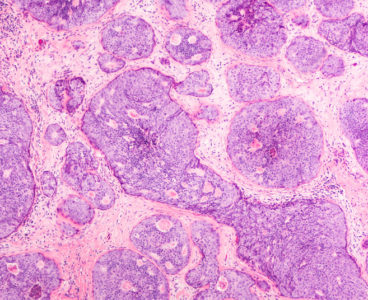

New insights into how cancer cells fuel their growth are opening novel possibilities for cancer treatment. A team of researchers at Baylor College of Medicine and Roswell Park Comprehensive Cancer Center has identified a long sought after connection between how cancer cells use the sugar glucose to generate energy – the Warburg pathway – and…

A new laboratory technique developed by researchers at Baylor College of Medicine and other institutions can rapidly test the effectiveness of treatments for life-threatening breast cancer metastases in bone. The study appears in Nature Communications. “For a number of breast cancer patients, the problem is metastasis — the dissemination of breast tumor cells to other organs…